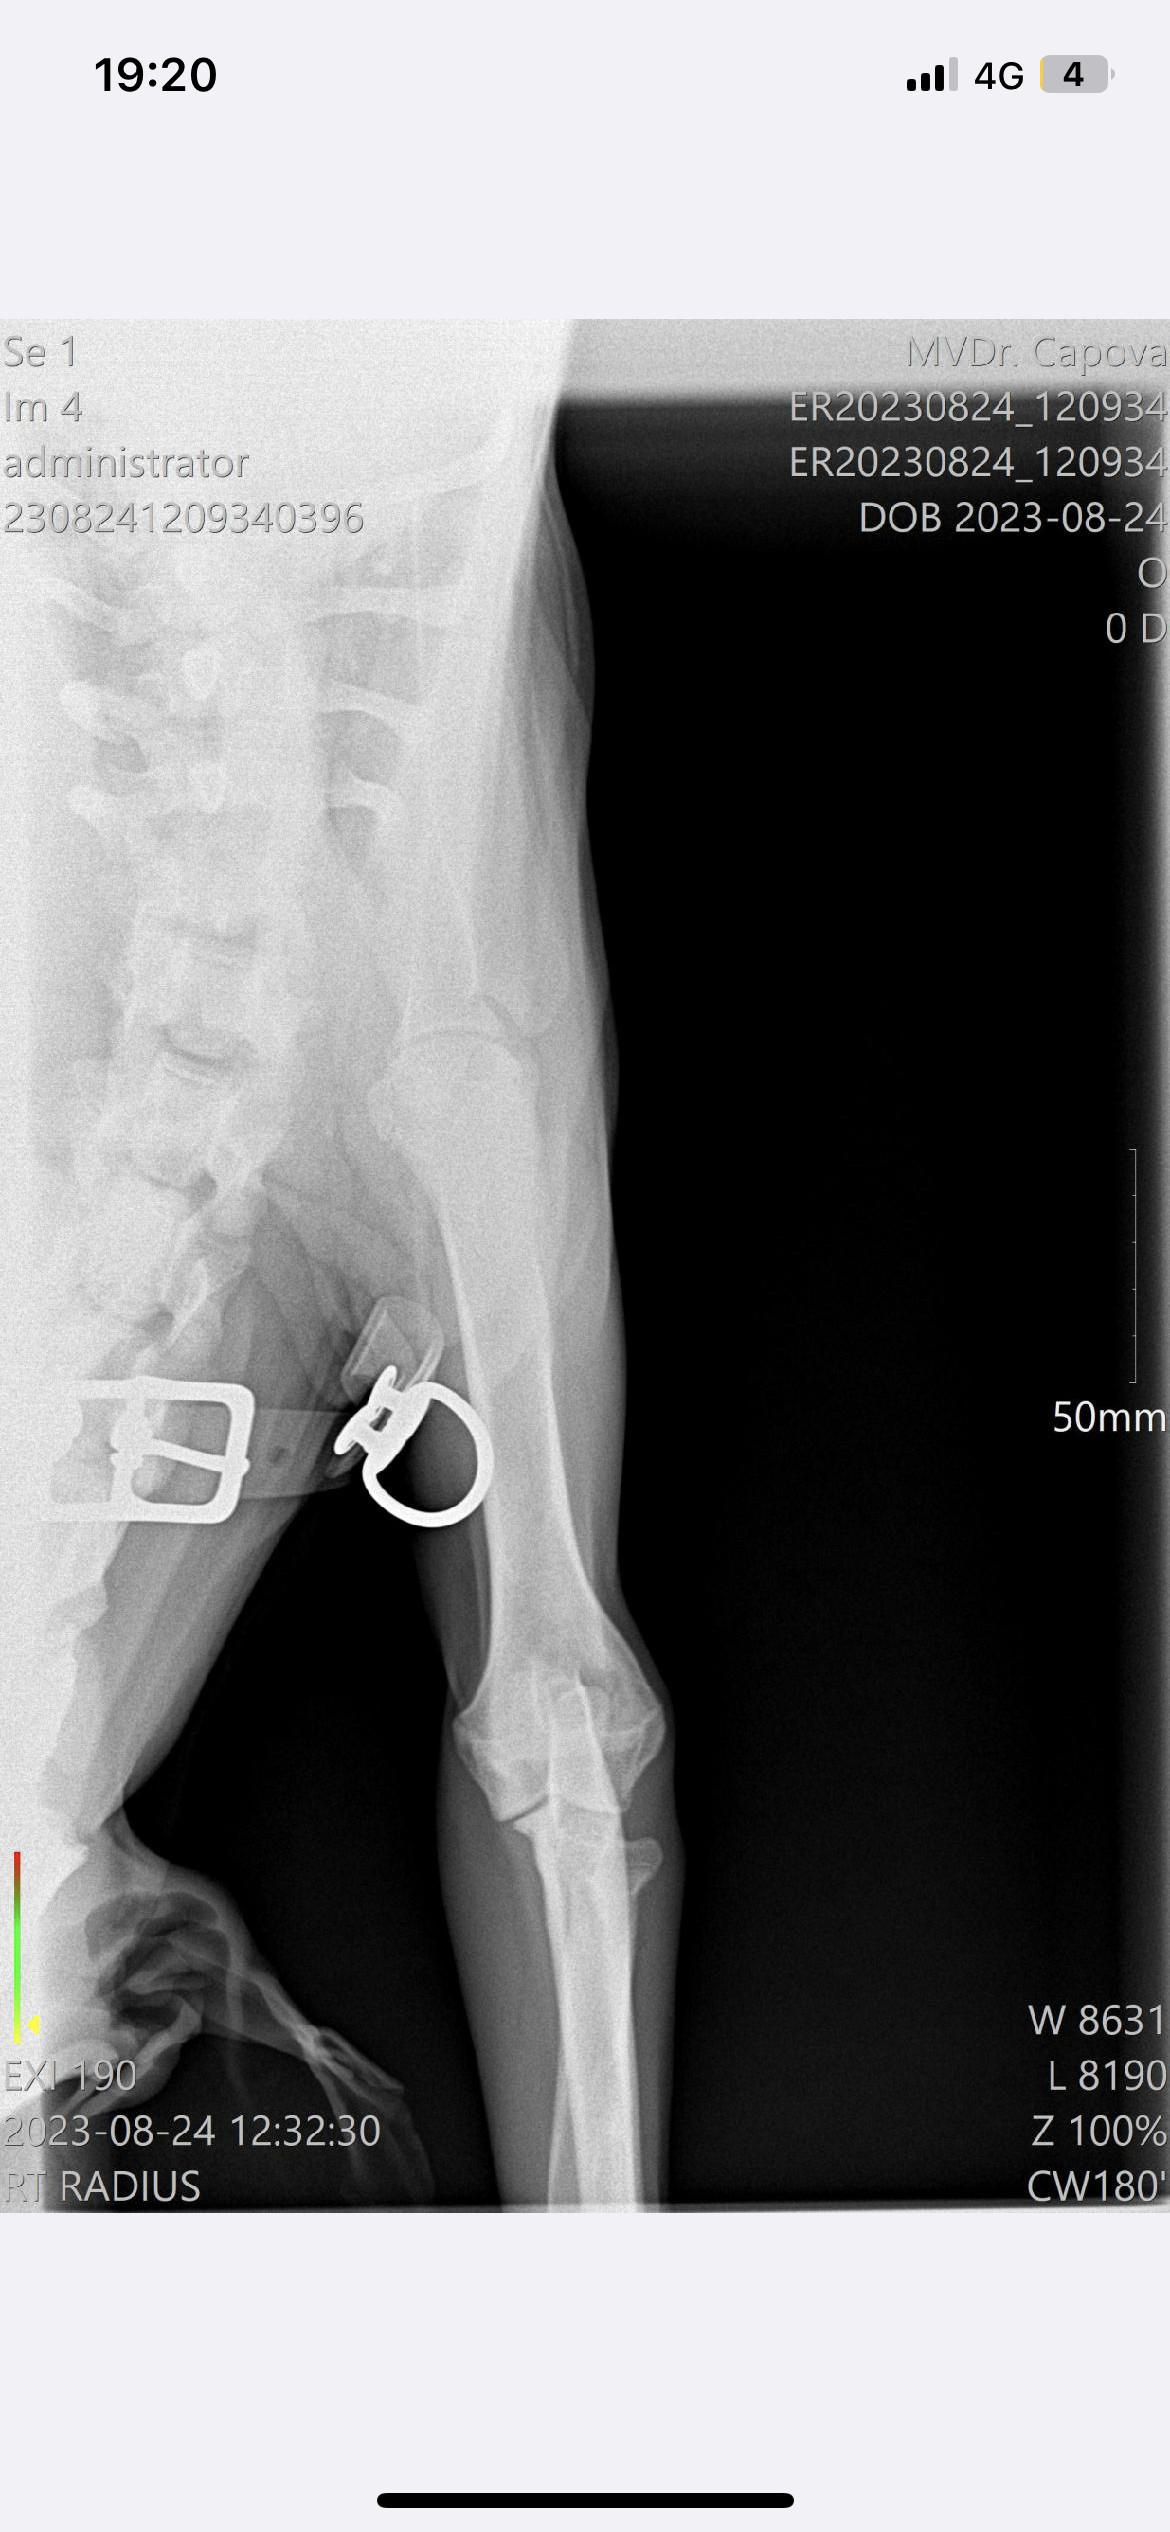

Operace a léčba pro Barlettku

Představení sbírky

Komu pomůžeme?

Na co konkrétně budou peníze z této sbírky použity?